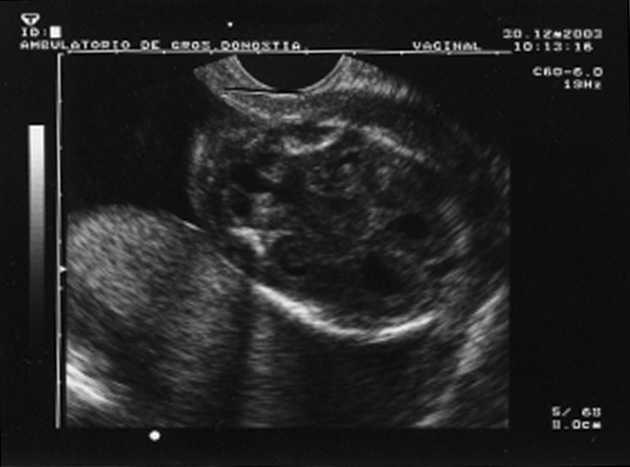

Al cabo de una semana se repite la ecografía, con los siguientes hallazgos: frecuencia cardíaca fetal (FCF) positiva; feto en posición cefálica; sexo masculino. peso fetal en percentil 10-25; aumento generalizado del espacio subaracnoideo, con aspecto de parénquima encefálico de pequeño tamaño y con escasas circunvoluciones; se observa comunicación entre las astas anteriores de los ventrículos laterales; cerebelo de morfología anómala con ausencia parcial de vérmix cerebeloso y cisterna magna límite; notable hiperecogenicidad intestinal; líquido amniótico normal. El diagnóstico fue: variante de Dandy-Walker + aumento de espacio subaracnoideo + holoprosencefalia lobar + hiperrefringencia intestinal (figs. 1 y 2).

Figura 2. Hiperrefringencia intestinal.

-- Hiperrefringencia intestinal.